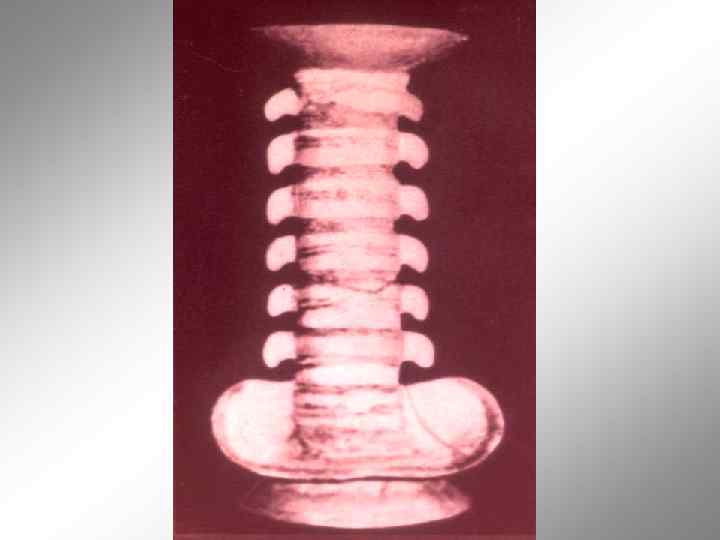

Структурные и функциональные нарушения позвоночника. Остеохондроз. N. Andre‘ Эмблема ортопедии (1741) Профессор А. Д. Ченский